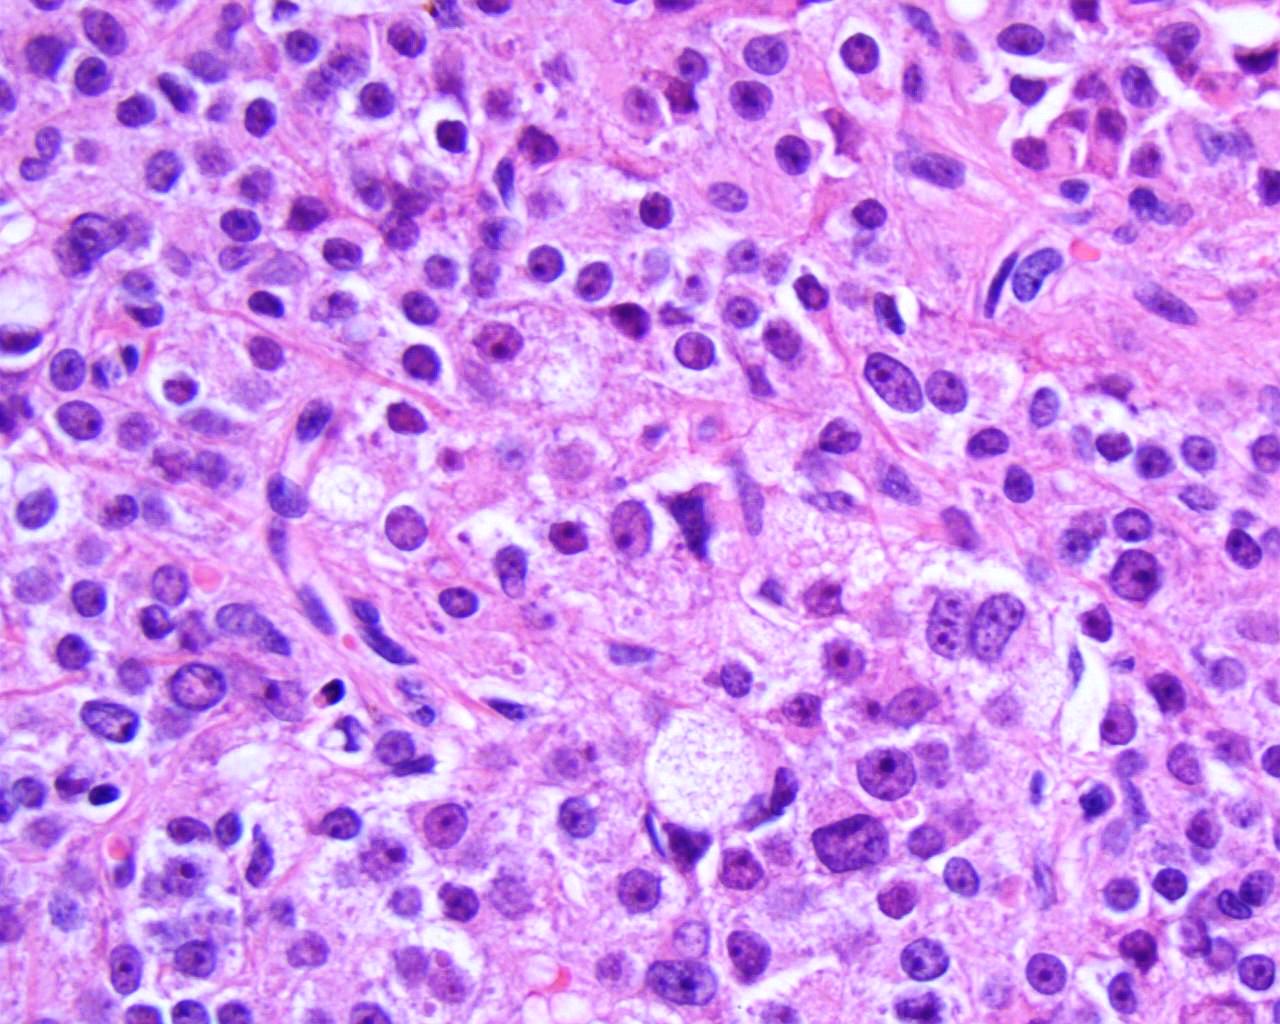

Raziskovalke in raziskovalci so ugotovili, da razmnoževanje virusa tudi po preboleli okužbi omogočajo Leydigove celice, ki se nahajajo med semenskimi cevkami v modih in proizvajajo testosteron. Poleg znižane koncentracije testosterona v mišjih samcih so dokazali tudi zmanjšano izražanje genov za njegovo sintezo v Leydigovih celicah. Iz rezultatov lahko sklepamo, da do zmanjšanja velikosti testisov pride zaradi znižane ravni testosterona, ki ga ob okužbi z virusom Zika Leydigove celice manj izločajo.